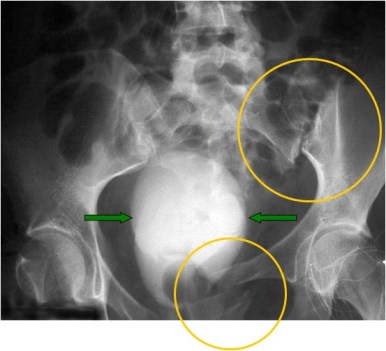

SIGNO DE LA VEJIGA DE PERA

Los traumatismos pélvicos, las adenopatías ilíacas bilaterales, la lipomatosis pélvica y otros procesos, producen una compresión bilateral de la vejiga, que adopta forma de lágrima o de pera.

En la imagen vemos la vejiga de pera en un paciente con traumatismo pélvico. Puede verse la fractura de la rama iliopubiana izquierda y la fractura de ala sacra con luxación sacroilíaca izquierda.